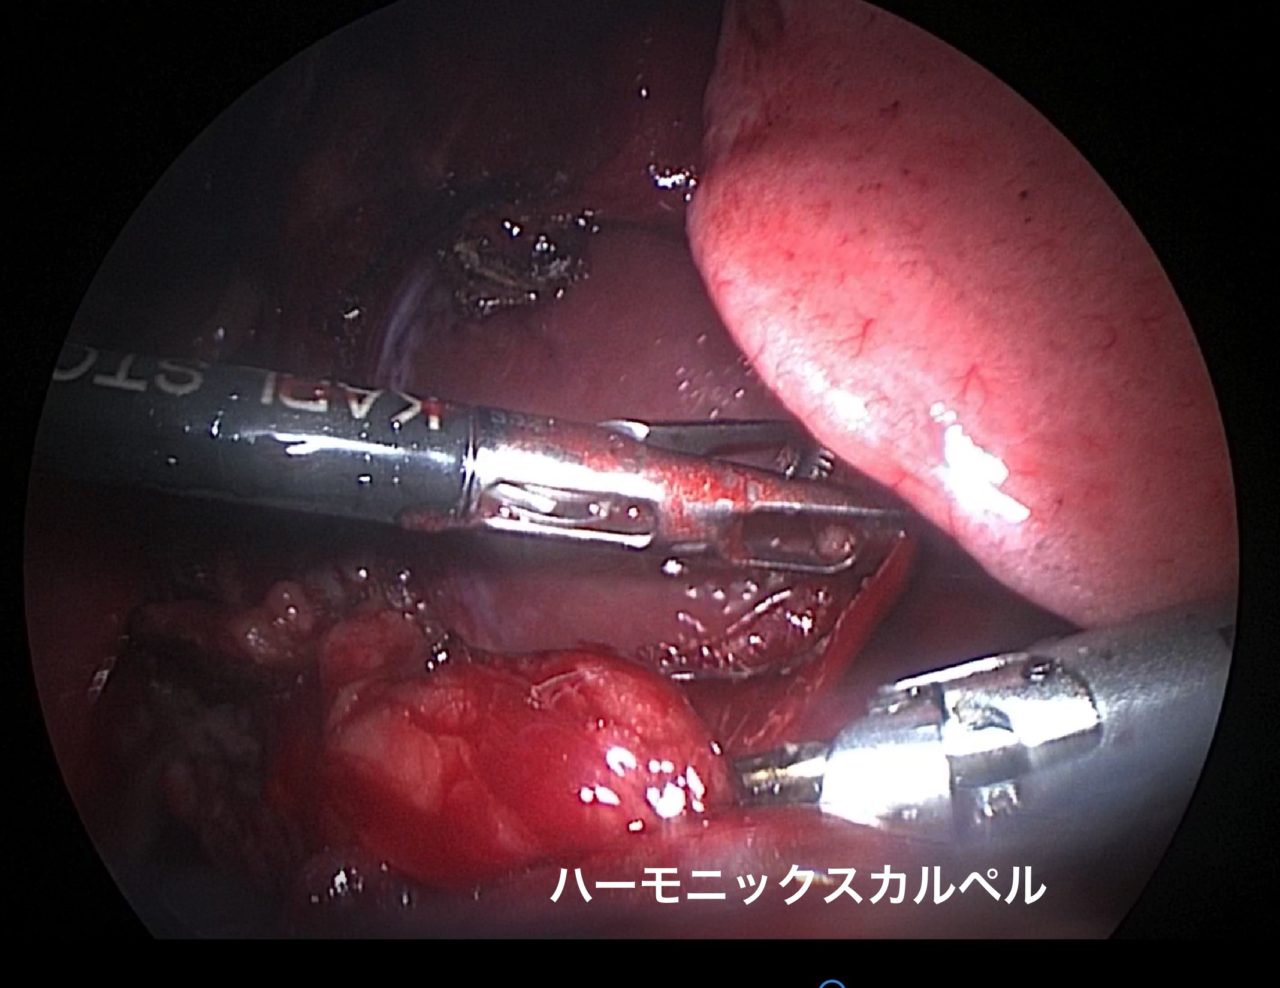

ゴールデンレトリバーは血管肉腫の好発犬種です。特に右心耳、肝臓、脾臓などに発生する事が知られています。右心耳であれば心タンポナーデという状態を引き起こし、循環状態が悪化し低血圧となり突然倒れてしまいます。聴診でマッフルサウンド、心電図では電気的交互脈、胸部エックス線ではムーンハートを呈しています。超音波で拡張期に右心房が虚脱する様子が確認されます。心嚢内圧を下げるために、直ちに心膜穿刺術で救命を行います。残念ながらこの腫瘍に対する根治的な治療方法はなく、進行すれば再発性の出血性心タンポナーデを何度も繰り返す(何度も倒れる)ことになります。そこで、姑息的な手段ですが心膜切除術を行なっておけば心タンポナーデを回避する事が出来ます。近年、テクノロジーの発展とともに開胸術ではなく胸腔鏡を使って小さな傷で手術を行う事が可能となっています。この病気は突然ワンコを襲い、見つかった時はすでに進行している事がほとんどです。だからこそ、最小侵襲で最大の効果が期待できる胸腔鏡下心膜切除術に真の価値があると言えます。開胸術に比べ痛みも少なく入院も短くて済むからです。我々はたとえ根治不能な病気であっても、患者さんがQOLを保ちながらご家族との大切な時間を1日でも長く過ごせるように、チームで話し合いながら”より良い”を常に模索し続けます。